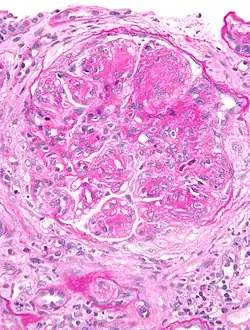

Micrograph of glomerulus in membranoproliferative glomerulonephritis with increased mesangial matrix and increased mesangial cellularity. Kidney biopsy. PAS stain.

The GBM is rebuilt on top of the deposits, causing a "tram tracking" appearance under the microscope.[17] Mesangial cellularity is increased.[18]